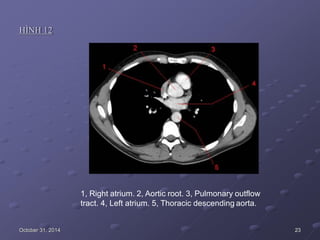

HÌNH 12

1, Right atrium. 2, Aortic root. 3, Pulmonary outflow

tract. 4, Left atrium. 5, Thoracic descending aorta.

October 31, 2014 23